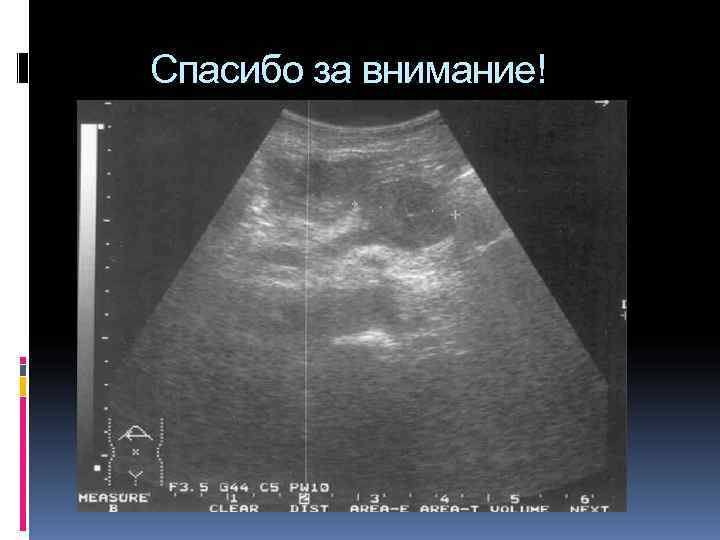

УЗИ исследование поджелудочной железы

Визуальная диагностика органов пищеварения УЗИ органов брюшной полости КТ органов брюшной полости МРТ органов брюшной полости Радиоизотопное исследование